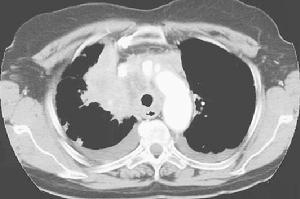

根據5例彩色超聲檢查均有肝靜脈狹窄閉塞,有2例伴肝段下腔靜脈狹窄。CT檢查2例,顯示肝尾葉代償性增大,增強掃描肝靜脈未顯示,奇靜脈和半奇靜脈擴張形成側支通道。MRI檢查1例顯示肝尾葉代償性增大,肝靜脈阻塞。下腔靜脈數字顯影(DSA)造影5例均未顯示肝靜脈,2例顯示肝靜脈開口“乳頭”征,2例肝段下腔靜脈狹窄,下腔靜脈側壓顯示狹窄兩端無明顯壓力差。經皮經肝穿刺肝靜脈造影顯示肝靜脈節段性阻塞2例,長0.5 cm~1.0 cm,膜性阻塞2例,4例均顯示肝靜脈擴張;1例顯示肝靜脈廣泛性閉塞,副肝靜脈細小並節段性閉塞。

先經頸靜脈途徑穿刺,行下腔靜脈造影,然後經皮經肝穿刺肝靜脈造影。肝靜脈膜性閉塞的2例,用硬質導管導絲順行開通肝靜脈後,建立經皮經肝肝靜脈頸靜脈導絲軌道,用0.5 cm~1.2 cm球囊行肝靜脈擴張成形。肝靜脈節段性狹窄閉塞的開通,用RUPS100肝穿裝置,在B超引導下經頸靜脈途徑,穿刺肝段下腔靜脈,建立經皮經肝肝靜脈頸靜脈導絲軌道,然後經頸靜脈途徑用0.5 cm~1.2 cm球囊進行擴張成形,或植入血管內支架。術後抗凝治療:肝素4 000 IU/d,靜脈注射1周后改口服阿司匹林和潘生丁,2個月後複查彩色超聲,了解肝靜脈通暢情況。